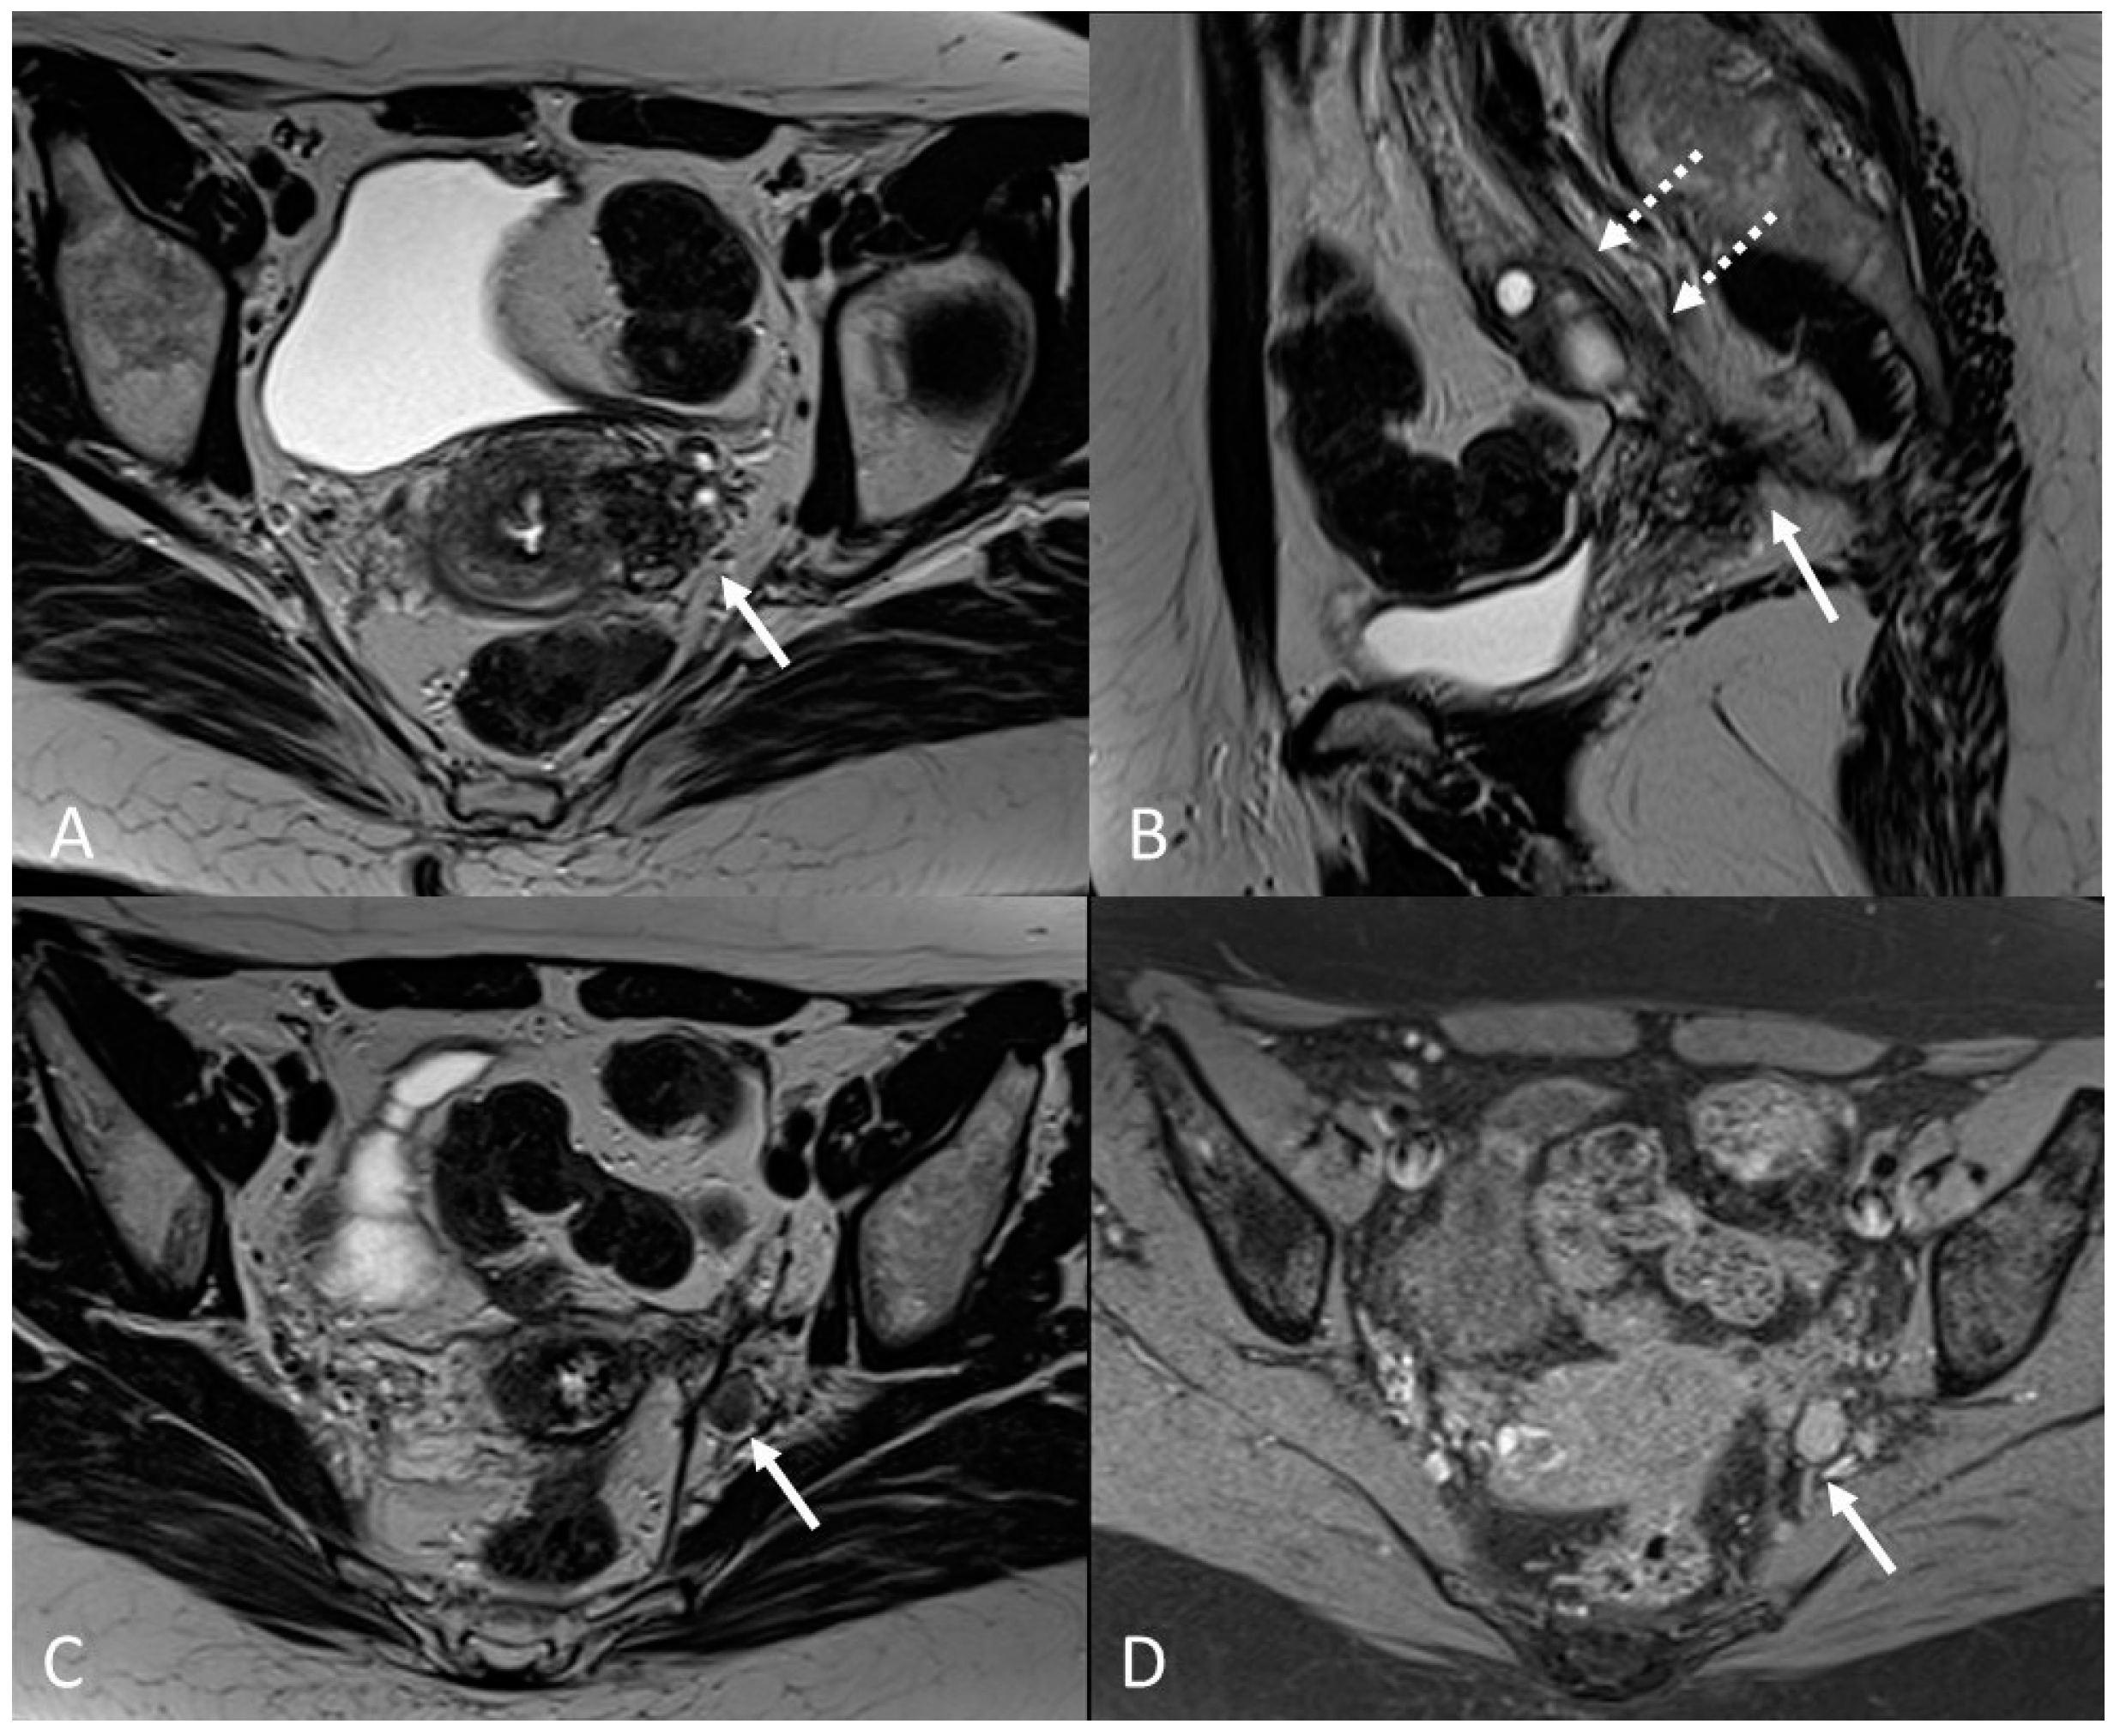

There are also cases of involvement of peripheral nerve plexuses of the pelvic region, such as sciatic, obturator, femoral, and pudendal nerves and their branches (Figure 14).

Figure 14.

Localization of the left sciatic nerve and para-uterine endometriotic nodule in a 43-year-olf female with a previously diagnosed endometriosis and surgery approach, accepted at the emergency department for reported left lumbar pain, which radiates to the left side and is associated with episodes of vomiting. (A) Coronal T2WI. Involvement of peripheral nerve plexuses of the pelvic region (sciatic nerve) appearing as a hypointense plaque (white arrow); (B) Coronal fat-suppressed T1WI. The lesion shows small hematic foci (white arrow); (C) Axial T2WI. Para-uterine endometriotic nodule (white dotted arrow) shows variable intensity ranging from low intensity (referred to as shading) to intermediate or high intensity; (D) Axial T1WI. Para-uterine endometriotic nodule with hyperintense signal (white dotted arrow).

MRI is the best imaging modality to investigate neural involvement [78].